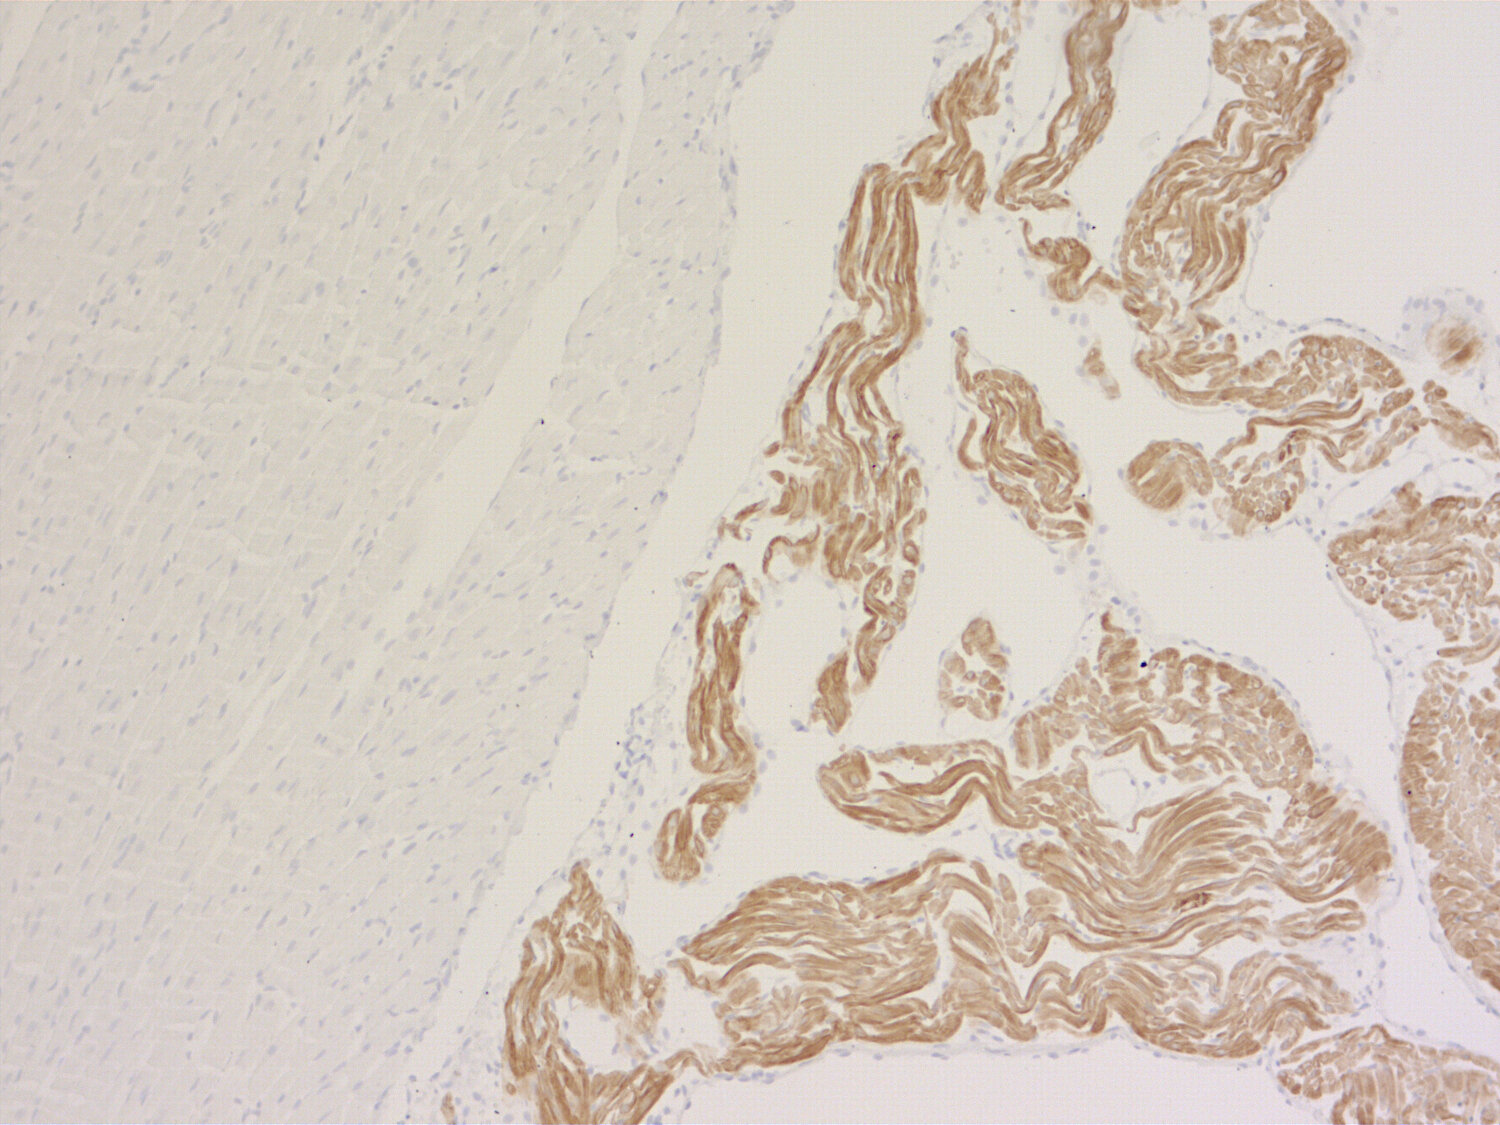

MLC-2A antibody - 311 018

IHC-P: 1 : 200 gallery

Immunohistochemistry (IHC-P) of formalin fixed, paraffin embedded (FFPE) tissue (some antibodies require special antigen retrieval steps, please refer to the ”Remarks” section). Immunoreactivity is usually revealed by fluorescence or a chromogenic substrate.

Specificity Specific for MLC-2A, no cross-reactivity to MLC-2V

During cardiogenesis two major isoforms of myosin light chain 2 are co-expressed in a tightly regulated manner. MLC-2A is only present in the atrium while MLC-2V is exclusively expressed in the ventricle. Knock out studies revealed that the 2A isoform cannot substitute for the 2V variant in the ventricular chamber.

This monoclonal antibody is a useful tool to distinguish between ventricle and atrium specific cardiomyocytes.